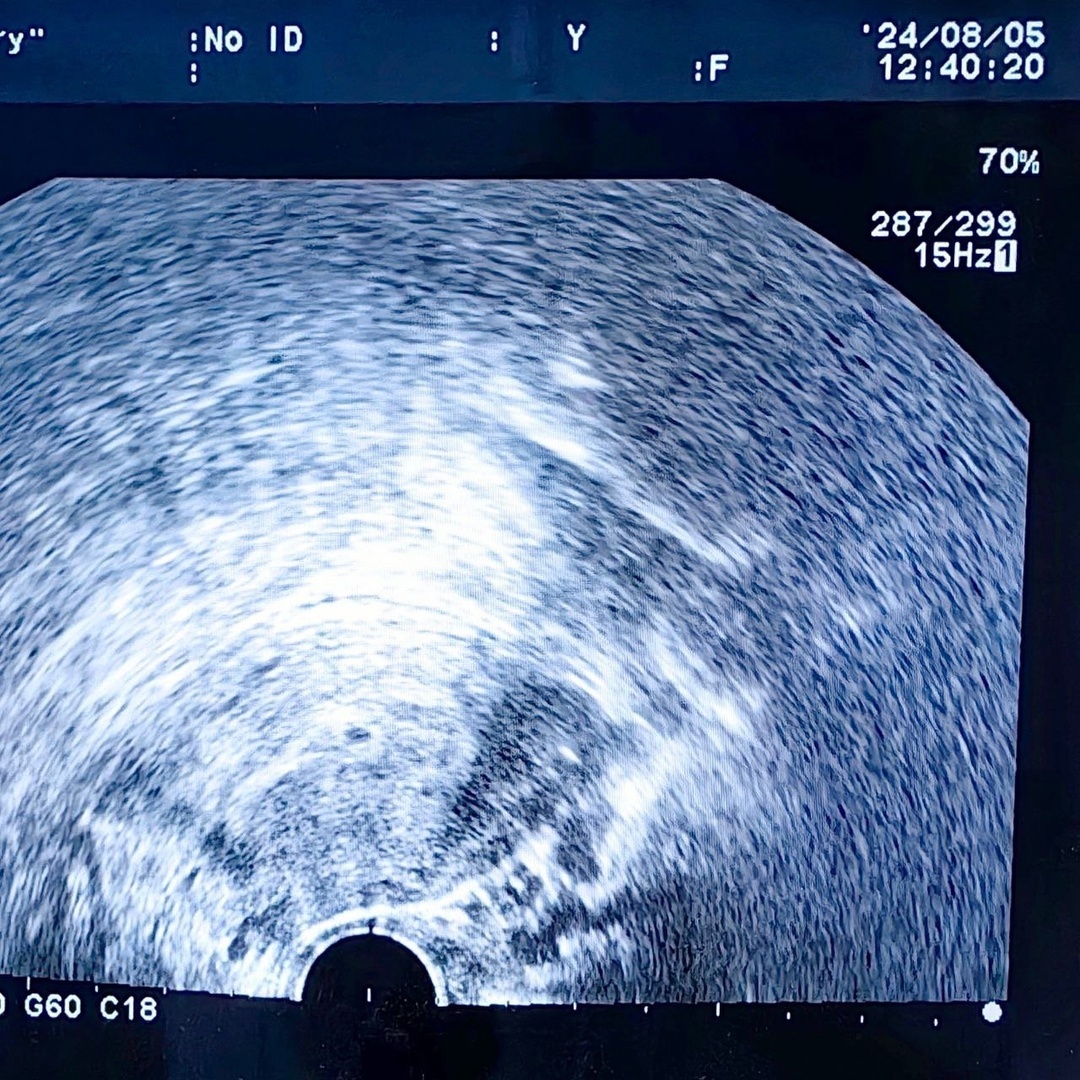

Низкий фолликулярный резерв и возраст за 40+ не означают невозможность зачатия.

Сегодняшняя маленькая «капелька» в эндометрии тому подтверждение.

И вот сегодня счастье счастливое. При задержке всего на три дня определяется маленькая бусинка.